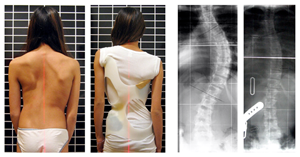

特發(fā)性脊柱側(cè)凸是脊柱的側(cè)偏畸形,原因不明。因為還有脊椎旋轉(zhuǎn)而不僅僅是偏離,所以術(shù)語脊柱側(cè)彎也被用來描述畸形。

在 X 線平片上,脊柱側(cè)彎定義為偏離度大于 10 度。

青少年特發(fā)性脊柱側(cè)彎的特征是脊柱三維畸形伴有側(cè)彎加椎體旋轉(zhuǎn)。

身體檢查涉及姿勢和身體輪廓的基線評估。

注意雙肩是否不平,是否有肩胛骨突出。

當(dāng)后肋骨在曲線的凸側(cè)向后推動時,可能會出現(xiàn)肋骨隆起。

特發(fā)性脊柱側(cè)彎有四種模式